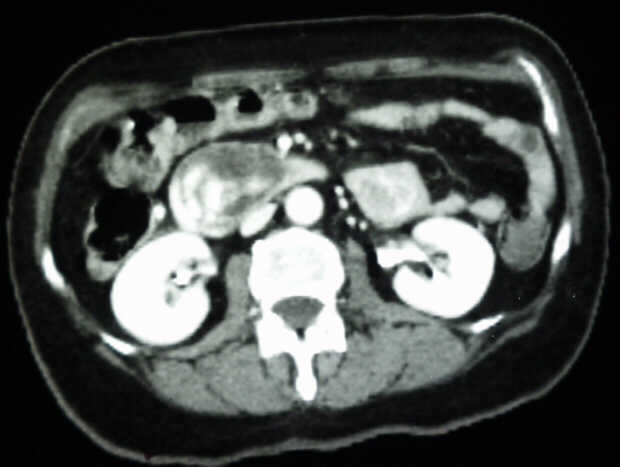

Diagnosis: Angiography

Giuseppe Morelli Coppola, Raffaella Niola, Franco Maglione

Unità Operativa di Radiologia Vascolare ed Interventistica, Azienda Ospedaliera "A. Cardarelli". Napoli, Italy